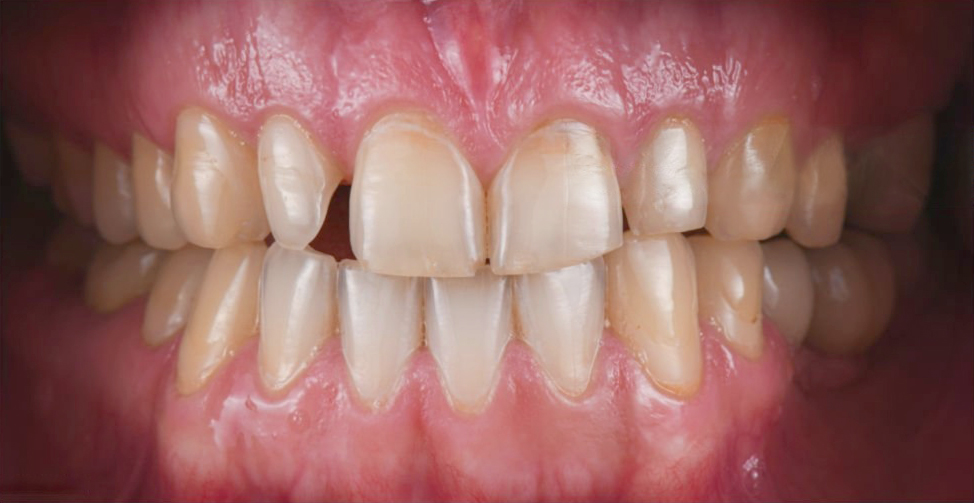

牙周病治療前、後的差別

治療前

治療後

牙齦呈現暗紅色發炎、牙齦腫大,容易

有滲出液與流血

牙齦呈現淡粉紅色、牙齦消腫不易流血